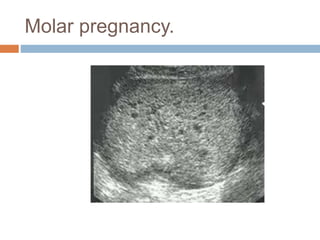

Molar pregnancy.